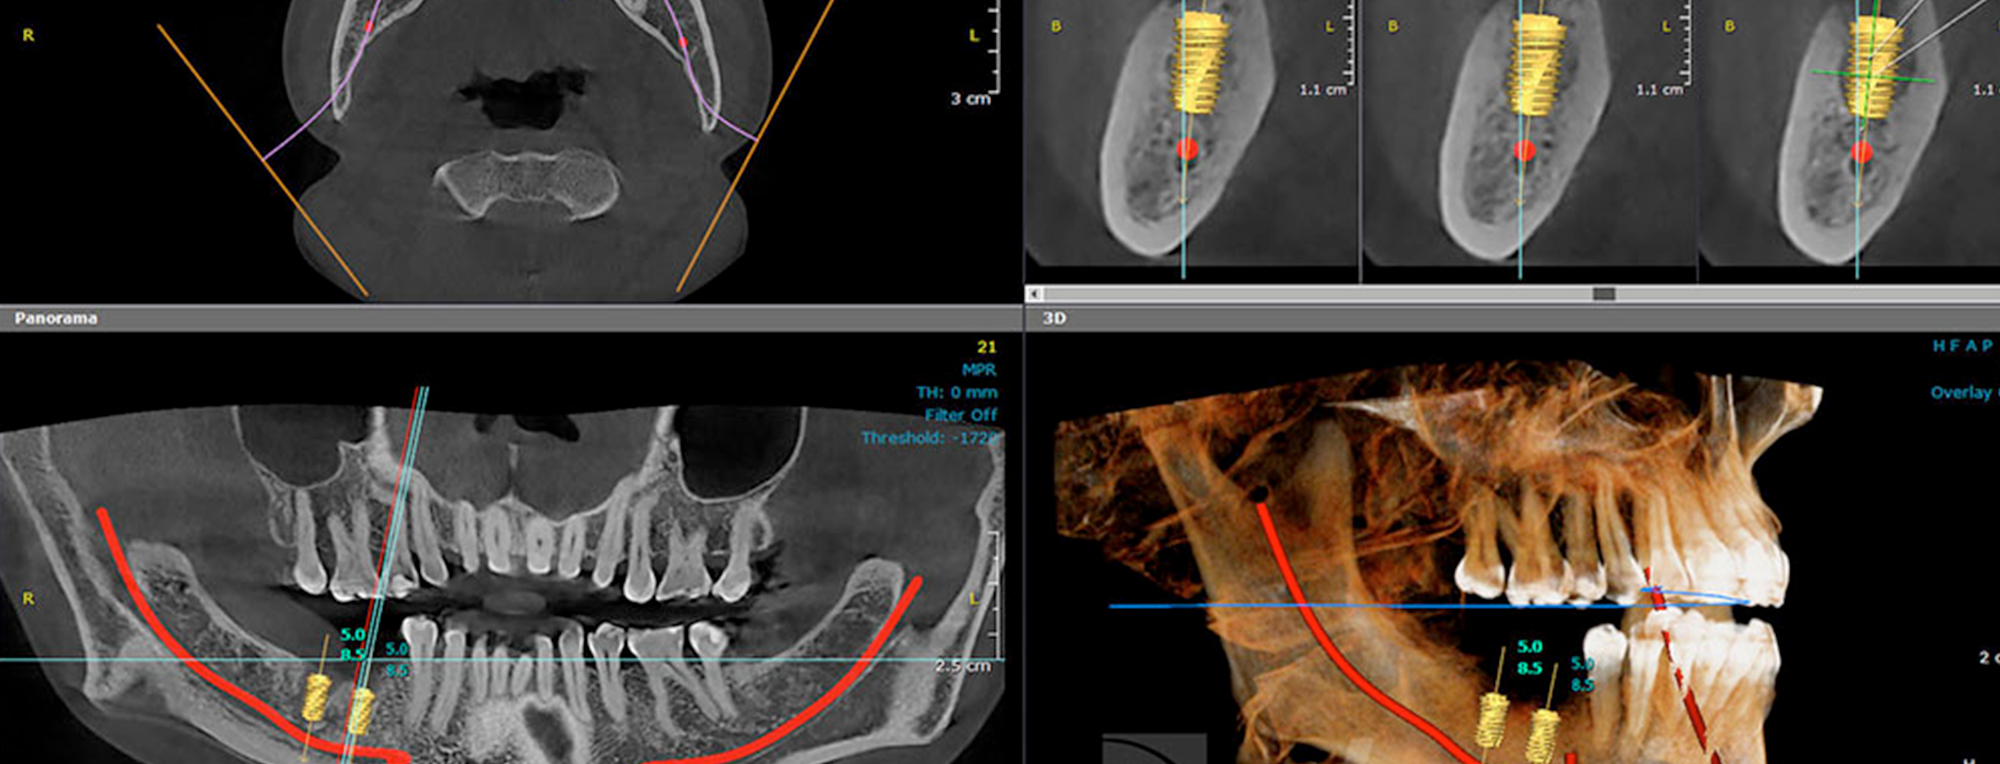

A diferencia de la radiografía panorámica, la Tomografía Computarizada (TAC) genera imágenes tridimensionales. Esto permite una visión detallada y precisa de las estructuras óseas, tejidos blandos, y vías nerviosas, algo crucial para planificar procedimientos complejos como ortodoncia, implantes o endodoncias.

• Visualización en 3D: Permite ver con mayor claridad posibles infecciones, daños en el hueso, y la ubicación de los nervios.

• Mayor precisión en tratamientos complejos: Ideal para cirugías, implantes y otros tratamientos invasivos, donde la ubicación exacta de los nervios y huesos es clave para minimizar riesgos.

• Mejor planificación del tratamiento: La TAC ofrece al odontólogo la información necesaria para diseñar un tratamiento más efectivo y personalizado.